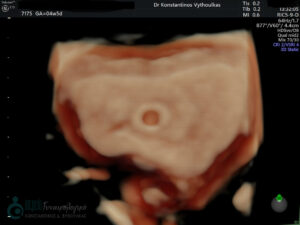

- Υπερηχογραφική εξέταση, η οποία συμβάλλει στη διαπίστωση της ενδομήτριας κύησης και αποκλεισμό της έκτοπης κύησης. Επιπλέον, μπορεί να διαπιστώσει εάν πρόκειται για μονήρη ή πολύδυμη κύηση, να ανιχνεύσει την εμβρυϊκή καρδιακή λειτουργία μετά τις 6 εβδομάδες και να προσδιορίσει υπερηχογραφικά την ηλικία κύησης, με βάση το κεφαλουραίο μήκος του εμβρύου μετά τις 8 εβδομάδες.